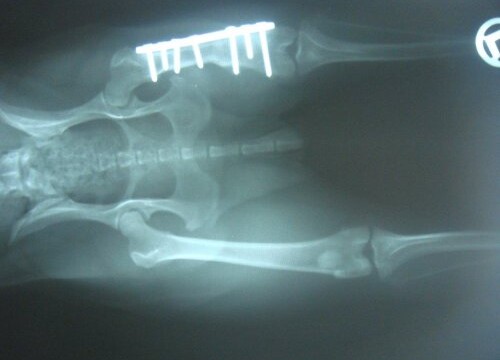

Alle Welpen wurden vermittelt und Tilly wurde am 21.12.2012 bei Dr. Rumpf operiert. Sie hatte einen alten Oberschenkelbruch im linken Hinterbein.

Die OP ist gut verlaufen, Tilly hat eine Platte bekommen und muss im September 2013 nochmals operiert werden. Dabei wird die Platte dann wieder entfernt.

Da der Bruch vermutlich schon mind. ein halbes Jahr alt war, musste bei der OP bei beiden Knochenenden 1,5 cm abgeschnitten werden. Dadurch ist ihr linkes Hinterbein nun verkürzt und Tilly wird immer humpeln. Aber mittlerweile verwendet sie ihr Bein schon wieder mehr.

Ein Kontrollröngten im Jänner 2013 zeigte, das alles in Ordnung ist.

Tilly wurde am 19.2.2013 kastriert und da haben wir nochmal ein Kontrollröntgen machen lassen. Auf diesem Foto kann man sehr gut erkennen, dass der Knochen kürzer ist.